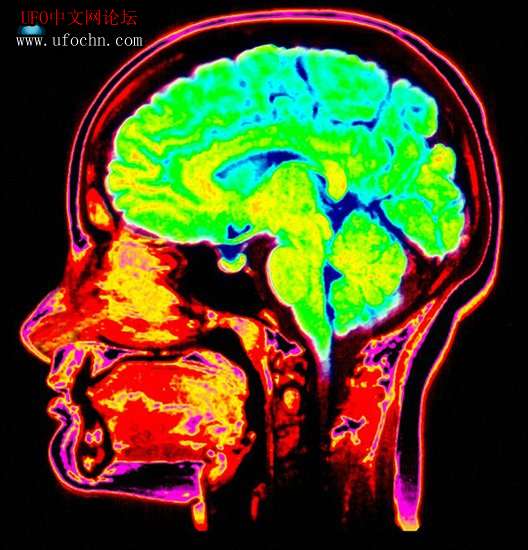

据英国每日邮报10月30日报道,通常多数人仅能回忆起睡梦中的片断内容,但目前科学家最新研制的新型装置或将完全复制人们的梦境。  科学家预测我们不久便能使用计算机“看到”自己的梦境内容,甚至人们还能将昨天的梦境复制出来进行观看。德国慕尼黑市马克斯-普朗克协会物理学家表示,他们已证实新型大脑扫描器能够看到神智清晰造梦者的梦境。这意味着近期使用大脑监控器可阅读清醒状态人们思维的新途径又获得新的突破,该技术也可应用于解析呈现人们的梦境。

马克斯-普朗克协会科学家证实扫描神智清晰造梦者大脑的梦境就像扫描其清醒状态大脑思维一样,这项最新研究发表在《当代生物学》杂志上,可用于展示建立动态人类大脑梦境图像的“复原技术”。

科学家使用核磁共振成像和近红外线光谱仪来监控造梦者头部的热量变化,从而显示出大脑活跃性。当造梦者做梦时并未紧握手,但大脑扫描可以显示当他们紧握真实手和梦境虚幻手时大脑活跃性特征。